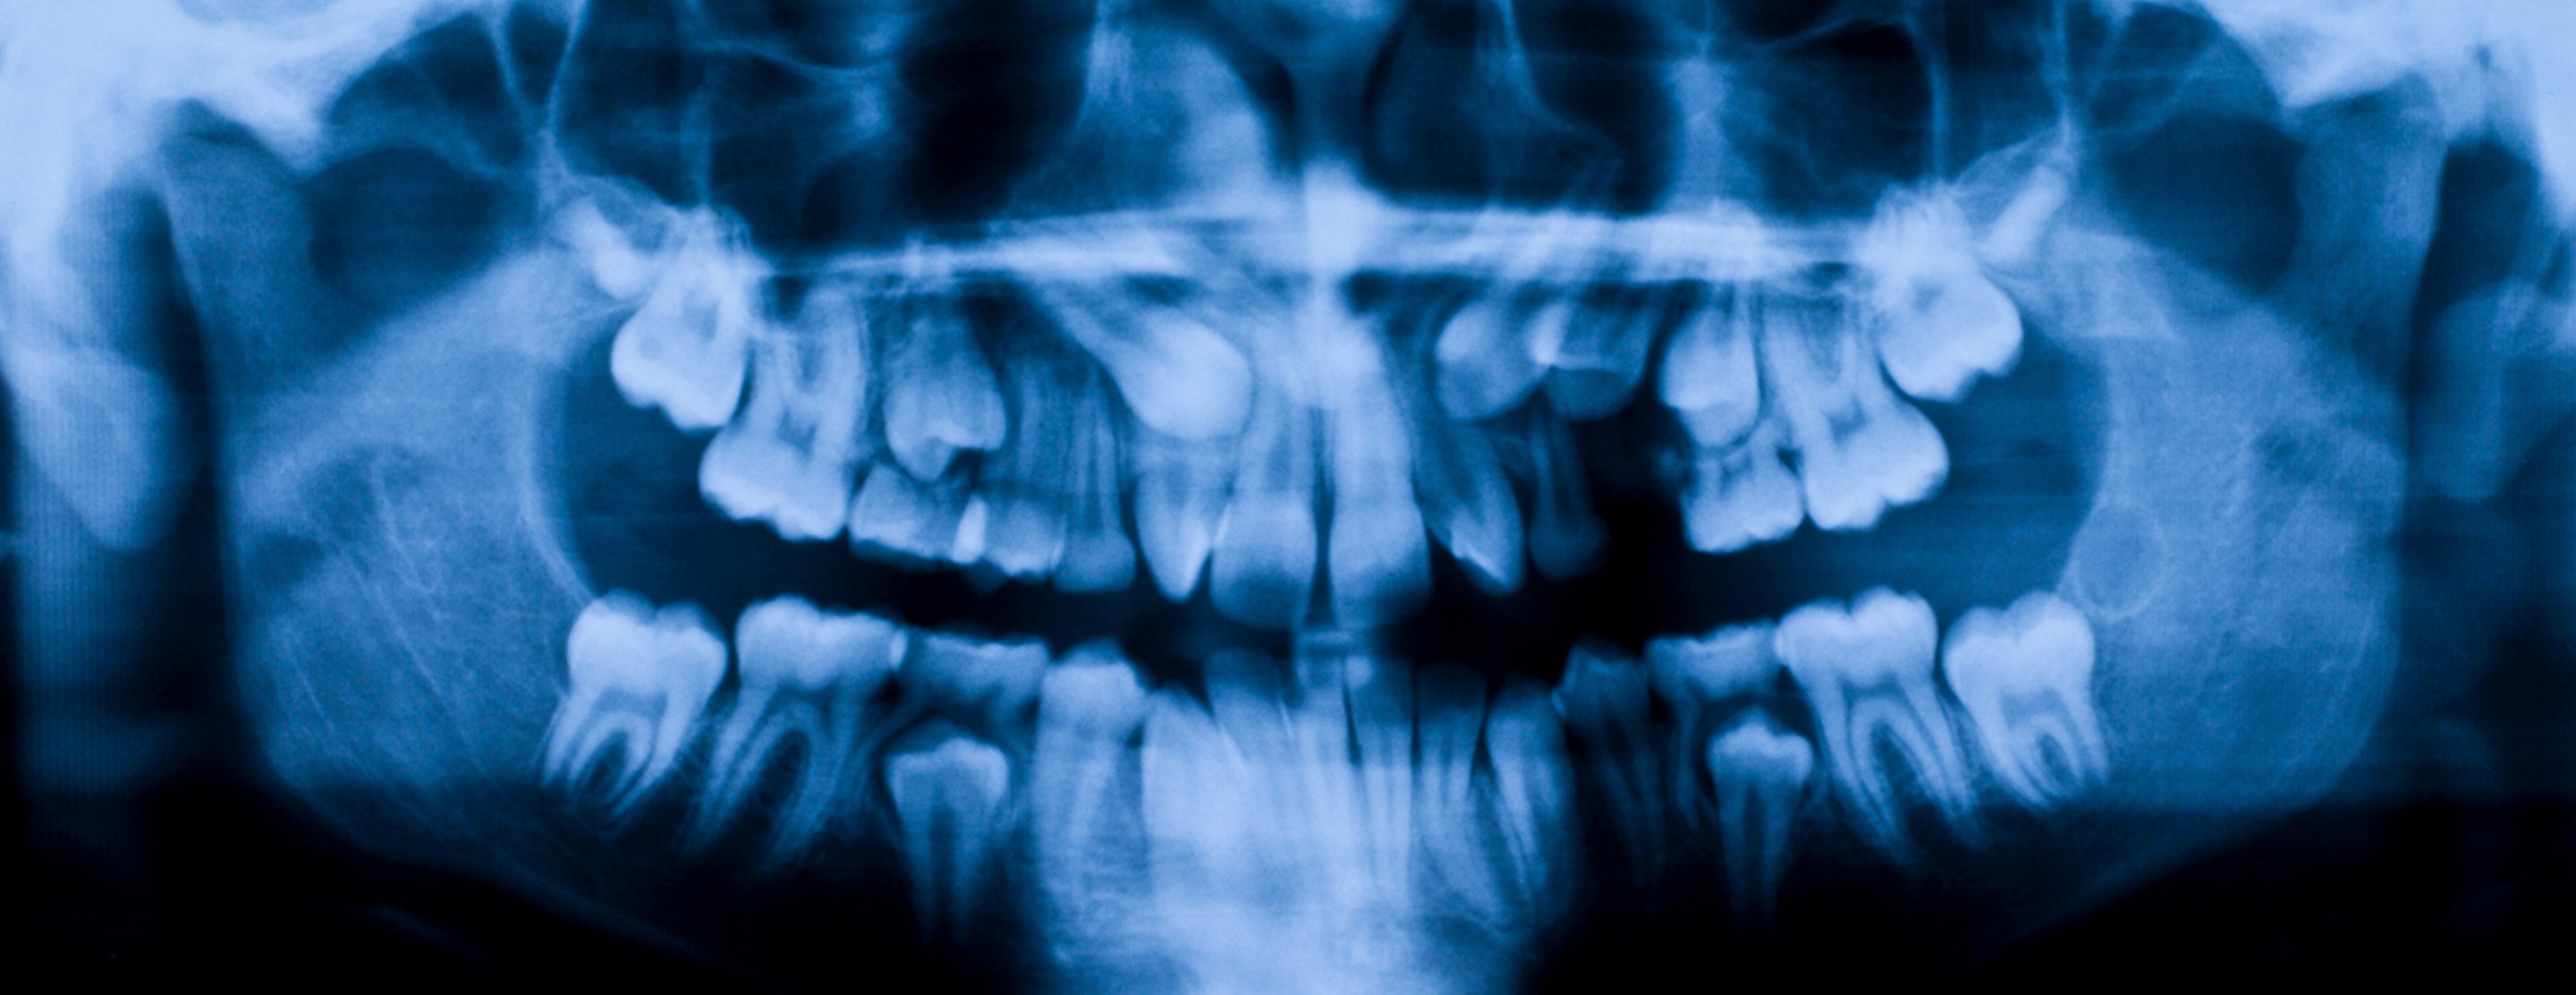

Dental x-rays are a type of image of the teeth and mouth. X-rays are a form of high energy electromagnetic radiation. The x-rays penetrate the body to form an image on film or screen. X-rays can be either digital or developed on a film.

Structures that are dense (such as silver fillings or metal restoration) will block most of the light energy from the x-ray. This makes them appear white in the image. Structures that contain air will be black, and teeth, tissue, and fluid will appear as shades of gray.

- Panoramic. Requires a special machine that rotates around the head. The x-ray captures all of the jaws and teeth in one shot. It is used to plan treatment for dental implants, check for impacted wisdom teeth, and detect jaw problems. A panoramic x-ray is not the best method for detecting cavities, unless the decay is very advanced and deep.